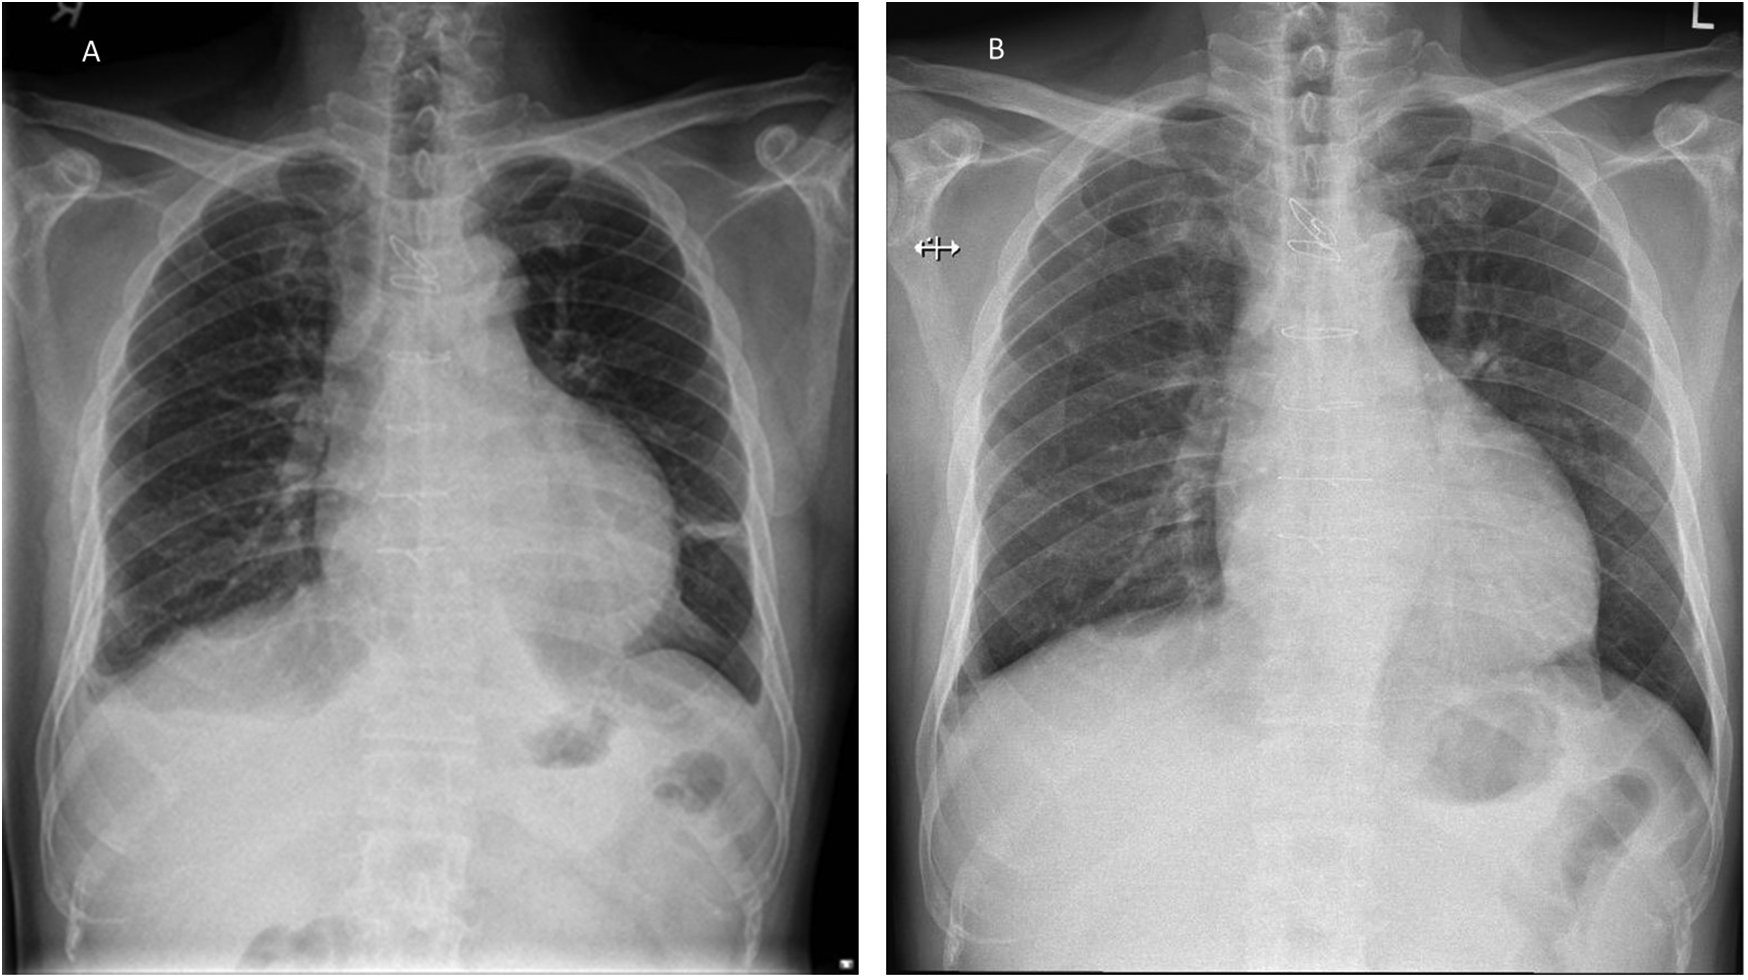

He underwent urgent pericardiocentesis, during which 600 mL of hemoserous fluid was drained, resulting in the relief of symptoms. The pericardial drain was inserted in the cardiovascular suite under sterile conditions. No routine antibiotics were given. The pericardial drain was left in situ for 2 days and was removed once no further drainage was observed. Microscopic analysis of the fluid drained showed a WBC count of 473/µL, with 75% lymphocytes and 17% polymorphs. Gram staining did not identify any organisms. Aerobic, anaerobic, and acid-fast bacilli cultures were also negative. Fluid analysis showed a fluid lactate dehydrogenase (LDH) level of 384 (serum 408) U/L and a fluid protein level of 57 (serum 76) g/L, fulfilling Light's criteria1 for an inflammatory effusion. The cytology report showed occasional reactive mesothelial cells admixed with scattered small lymphocytes, some macrophages, and neutrophils in a hemorrhagic background, with no malignant cells identified. The patient remained clinically stable and was discharged on day 3 of admission. He was reviewed at the clinic 5 days later, complaining of a cough with purulent sputum. He was afebrile, and the previous sternotomy and pericardiocentesis sites were clean. A chest x-ray was done, which showed fractured sternal wires (Figure 1).

Figure 1

Patient's chest x-ray. (A) CXR during his admission for pericardial tamponade showing a globular heart and small pleural effusion. (B) Outpatient CXR taken 8 days later, showing that the third and fourth sternal wires had fractured with widening of the fifth and sixth wires.

The cause of post-operative mediastinitis is generally presumed to be either the intraoperative introduction of infection into the mediastinum or the spread of infection from the surgical wounds to the mediastinum (6). However, our patient demonstrated several atypical features. He presented with late pericardial effusion and features of pericardial tamponade. He was clinically not septic and showed resolution of symptoms after pericardiocentesis. Furthermore, his pericardial fluid cultures were negative for bacterial growth, and initial blood investigations did not suggest any signs of an ominous infection. Nevertheless, his white blood cell count and C-reactive protein levels were slightly elevated. Had we monitored these daily, they might have indicated that an infection was brewing, triggering an earlier chest CT. The follow-up chest x—ray, performed 2 days before his second readmission, also showed sternal wire fractures. Sternal wire fractures may be seen before mediastinitis manifests clinically and should prompt further investigations.